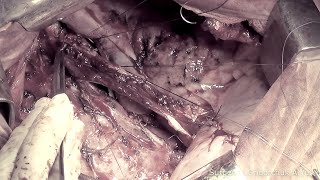

РНИОИ. Сюжет о профессоре Ю. Геворкяне и его пациентах. Вести. События недели.:

РНИОИ. Олег Кит. За пределами возможного:

Ростовский онкоцентр - Документальный фильм «История болезни»

Первый канал В Ростовском онкоинституте представили результаты масштабного исследования рака